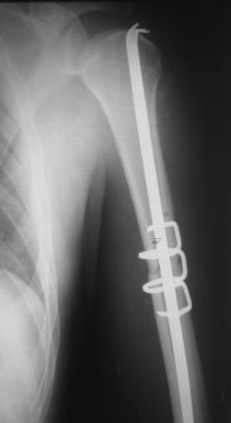

Здесь нет необходимости в серкляже. Вмешиваться на промежуточных отломках приходится, если есть угроза перфорации кожи, или промежуточный отломок попал в фасцию, как пуговица в петлю. В приложении сегментарный оскольчатый перелом плеча в проксимальном отделе, фиксированный больщеберцовым стержнем. Как видите, обошлось без серкляжа. Функция полная.

Пример отличный.

Вот что значит лечить перелом, а не рентгенограмму!

Александр, великолепные снимки! Вопрос - что за гвоздь?

Это укороченный большеберцовый стержень, которые делает предприятие "ЦИТО".

на синтезовский UTN похож))

Скажите пожалуйста, Александр Николаевич, почему Вы использовали большеберцовый гвоздь?

Доступные на тот момент гвозди для плеча имели худшие возможности фиксации в коротком проксимальном отломке.

Уважаемый Александр Николаевич! На продемонстрированных вами рентгенограммах имеется достаточно большое на мой взгляд смещение отломков после фиксации блокируемым гвоздем. На счет полной функции все понятно, а нет ли каких либо сосудистых расстройств конечности? Имею ввиду венозную недостаточность или лимфостаз.